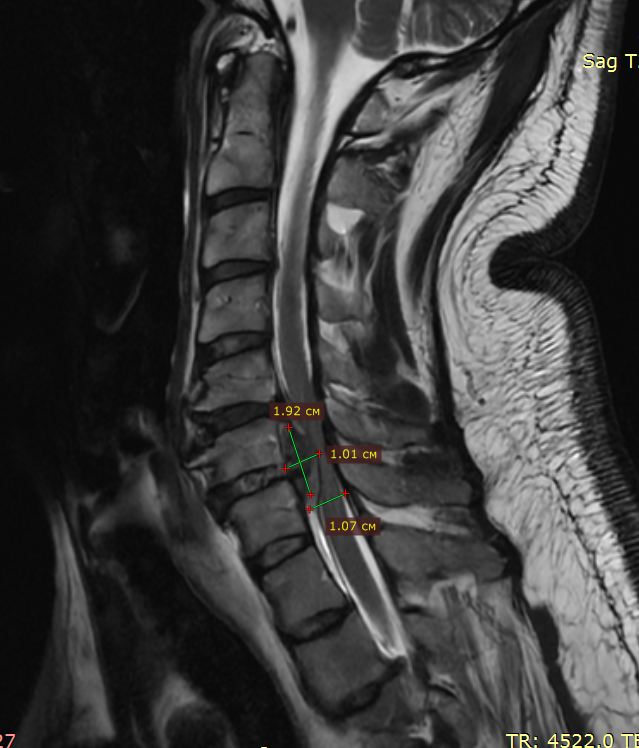

Из-за грыжи межпозвонковый диск полностью мигрировал в позвоночный канал, образовалась гигантская грыжа в шейном отделе на уровне С5-С6 позвонков. МРТ до операции

Из-за грыжи межпозвонковый диск полностью мигрировал в позвоночный канал, образовалась гигантская грыжа в шейном отделе на уровне С5-С6 позвонков. Размер грыжи составил около 2×1 см, но нужно понимать, что сама ёмкость канала на этом уровне составляет чуть больше сантиметра. Произошло сильное сдавление спинного мозга и его корешков, нервной ткани, что требовало срочного хирургического лечения в специализированной операционной», — объясняет к.м.н., заведующий отделением нейроортопедии Алексей Пелеганчук.